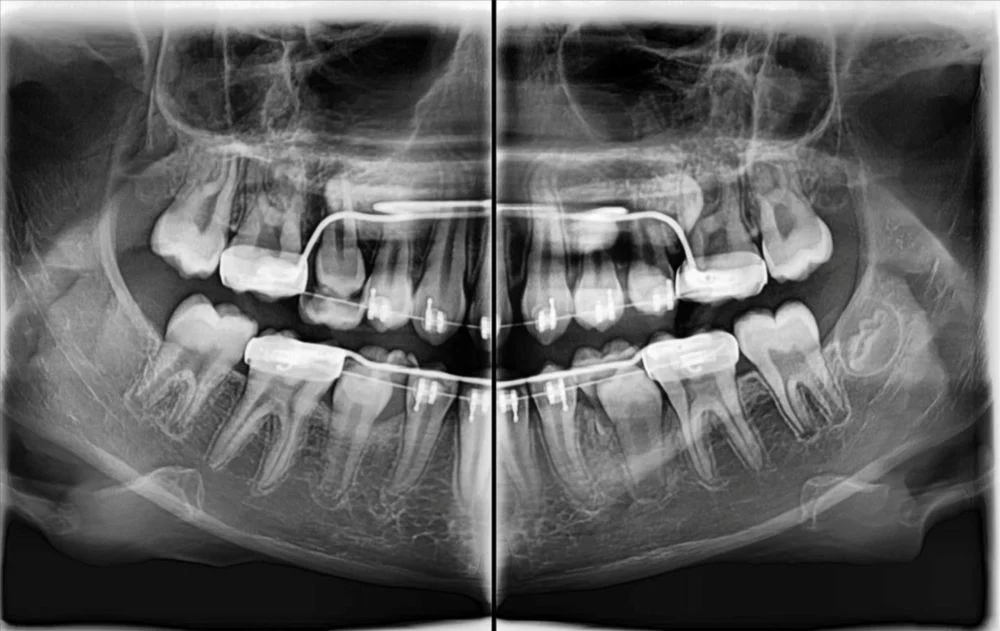

- wyraźne obrazy 2D i 3D — pomocne przy implantach, ósemkach, leczeniu kanałowym i ortodoncji

Pantomogram pokazuje cały stan uzębienia i kości — dzięki temu można wykryć zmiany, których nie widać na małym zdjęciu punktowym (jak torbiele, stany zapalne czy problemy ze stawami). To proste badanie, które warto wykonać profilaktycznie co kilka lat.

Tomografia CBCT tworzy trójwymiarowy obraz zębów, kości, zatok i stawów.

Pozwala na precyzyjne planowanie:

- implantów,

- usuwania ósemek,

- leczenia kanałowego,

- aparatów ortodontycznych,

- diagnostyki bólu zatok i stawu skroniowo-żuchwowego.